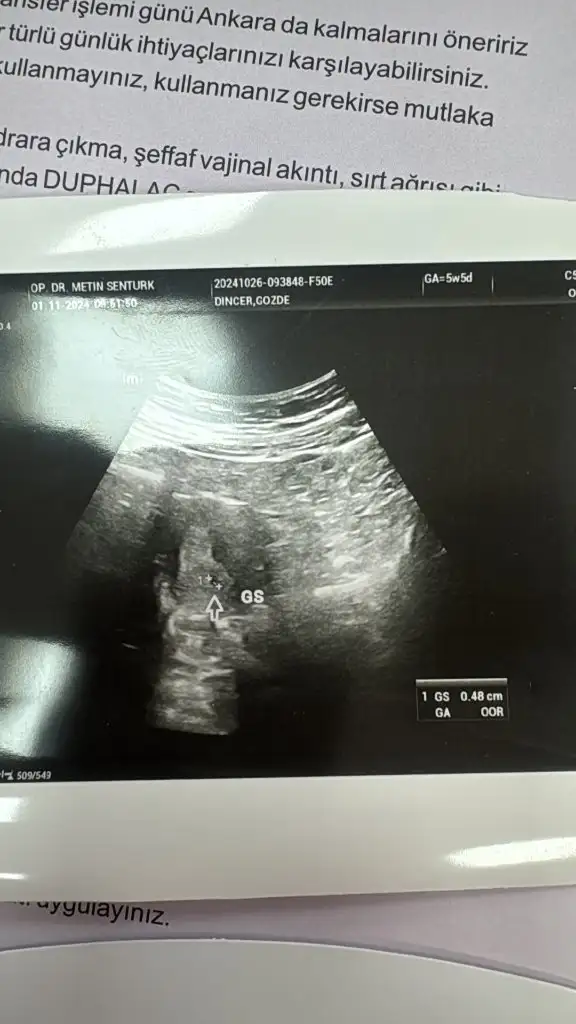

Hadi hayırlısı inşallah haftaya bebisinizi de görürsünüz ben de durum aynı bugün keseyi gördük şükür haftaya bebiş için gideceğiz Rabbim hepimizin emeklerini boşa cikarmasinKızlar selam transferimin 17. Günü

Keseyi gördü ultrasonla ama daha çok minnak olduğu için bebiş için haftaya gideceğim